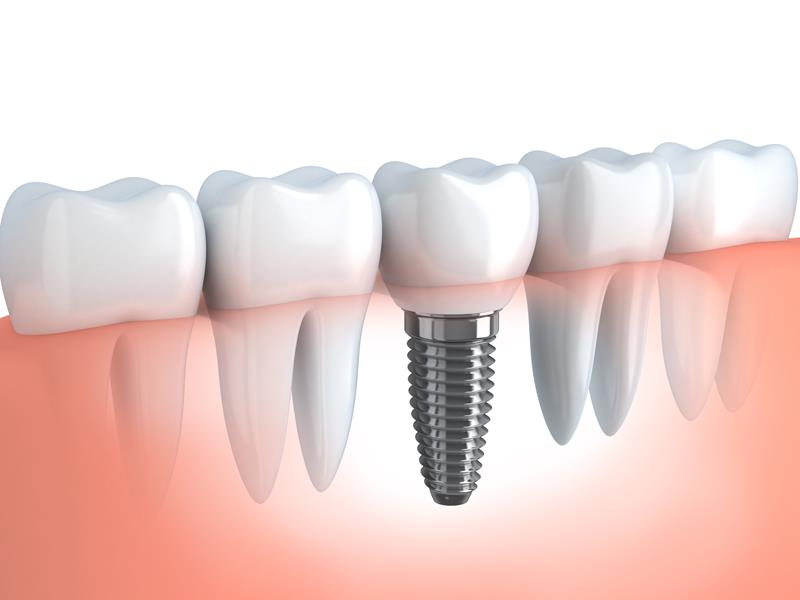

Dental Implants

When you have missing teeth, an alternative solution to dentures is dental implants. While dentures are removable, dental implants provide permanent new teeth to restore your mouth’s function and appearance. Dental implants tend to offer a successful and lasting solution to the loss of some or all of your teeth.